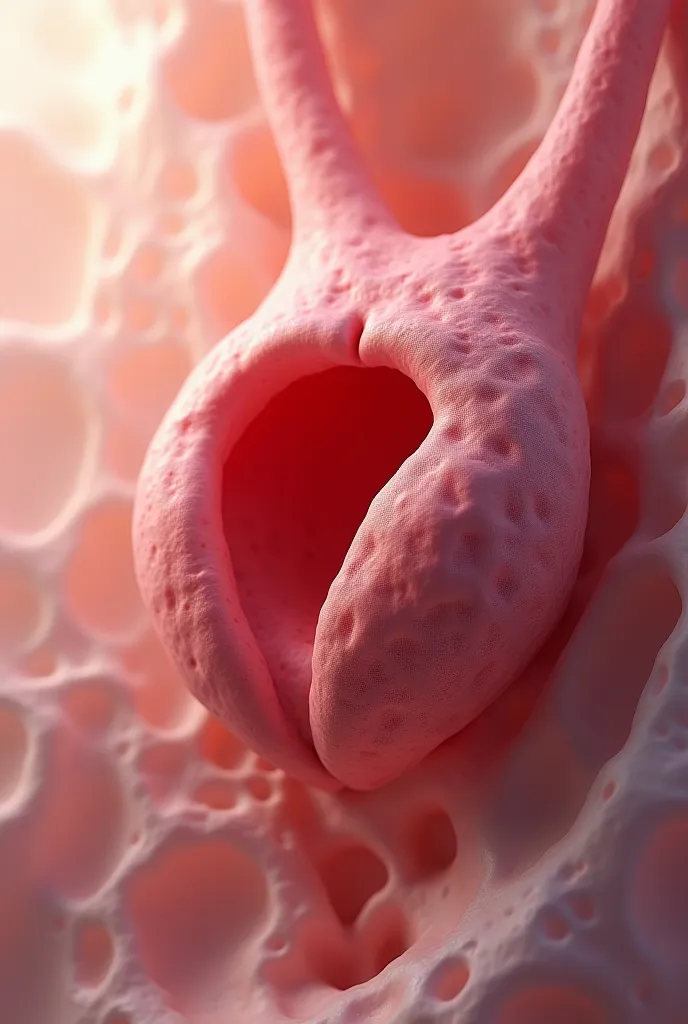

Pictures of swollen thyroid gland in neck, Use a Canon EOS 5D Mark IV with a 24

pictures of swollen thyroid gland in neck, Use a Canon EOS 5D Mark IV with a 24-70mm f/2.8 lens. Settings: ISO 100, aperture f/8, and shutter speed 1/125s to capture a sharp, vibrant image with a wide depth of field.

pictures of swollen thyroid gland in neck